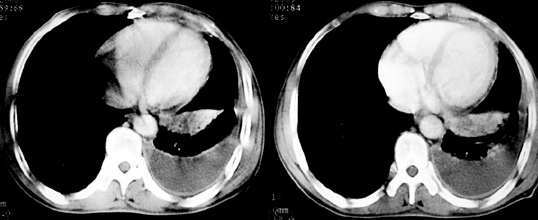

以下是引用jiajie在2005-11-6 22:07:00的发言:[br]1)左肺下叶阻塞性肺炎,胸腔积液,中心型肺癌可能大,建议纤支镜。[br]2)结合30年打石史,双肺弥漫性小结节考虑矽肺。

以下是引用sdqzwyx在2005-11-7 19:59:00的发言:[br]双肺弥漫大小不等的粟粒状结节影;肺纹理走行失去自然,粗细不均,边缘不规则,小叶间隔增厚;左上肺示不规则形致密影,从斑块边缘向周围伸出长短不一的致密索条影,临近的血管、支气管和叶间胸膜等结构受牵拉移位;左下肺示不规则团块状影,其内示空洞,洞内壁尚光整,左侧胸腔积液。右肺下叶背段亦示部分病灶融合。双肺可见局限性肺气肿。[br]诊断:结合病史符合三期矽肺表现(少数矽肺纤维斑块内可以形成空洞,一般认为是斑块中央感染引起坏死所致)但尘肺病人易合并肺结核,诊断可为三期+tb。所以此病人应进一步检查是否合并结核。